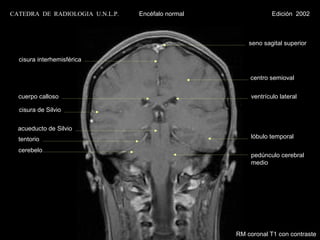

CATEDRA DE RADIOLOGIA U.N.L.P.   Encéfalo normal                Edición 2002

seno sagital superior

cisura interhemisférica

centro semioval

cuerpo calloso                                        ventrículo lateral

cisura de Silvio

acueducto de Silvio

tentorio                                              lóbulo temporal

cerebelo

pedúnculo cerebral

medio

RM coronal T1 con contraste